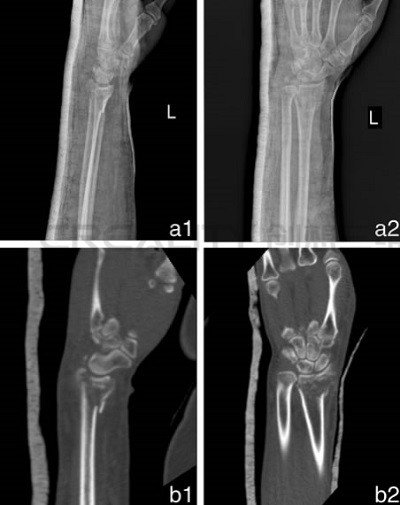

從以前跟蹤過(guò)的案例中,其中3D打印機(jī)已被用于創(chuàng)建假肢制造手臂模型以幫助修補(bǔ)骨折,甚至制作植入物來(lái)治愈損傷,但在本次研究中,研究人員評(píng)估了該技術(shù)在其中進(jìn)行改進(jìn)的能力。48名患有橈骨遠(yuǎn)端骨折的患者(最常見的上身?yè)p傷類型之一)參與了這項(xiàng)研究。

CT數(shù)據(jù)以DICOM格式存儲(chǔ),然后在3D打印機(jī)中使用PLA耗材打印之前通過(guò)Mimics軟件進(jìn)行轉(zhuǎn)換。科學(xué)家們報(bào)告了3D打印模型的成功,因?yàn)樗鼈兦宄仫@示了骨折的位置,這種手術(shù)每次大約需要兩個(gè)半小時(shí)。

“在3D模型上,我們根據(jù)骨折線分割骨折碎片,然后用K線暫時(shí)復(fù)位碎片,然后用金屬板和螺釘固定碎片,”研究小組說(shuō):“通過(guò)這種方式,所需植入物的類型和尺寸在術(shù)前確定,我們可以選擇合適的金屬板和螺釘。”